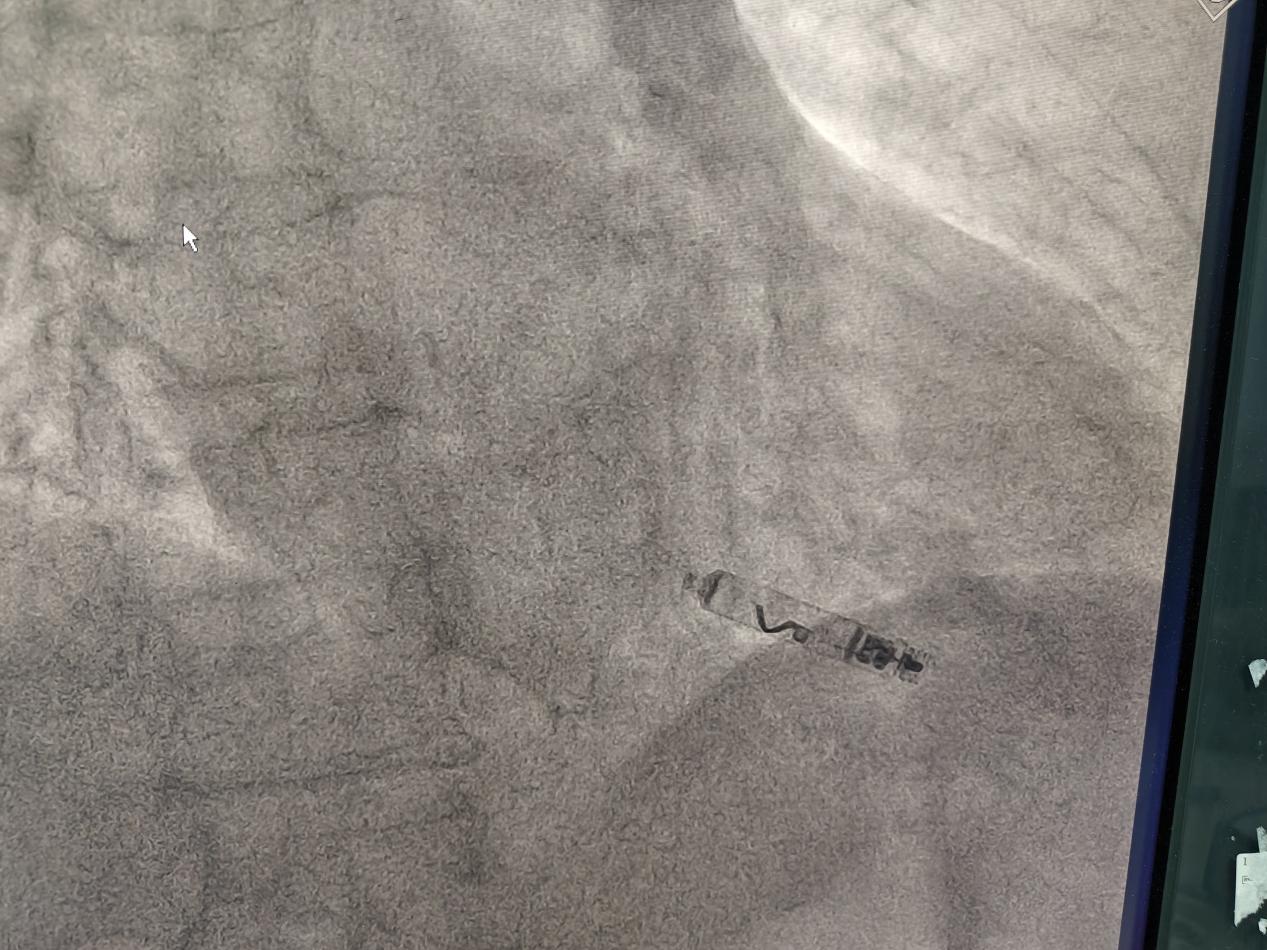

穿刺成功后,使用猪尾导管分别在RAO 30°、LAO 45°造影,RAO 30°右室大小显示清晰,LAO 45°间隔面显示清晰。

接好盐水管路,将起搏器激活后,将调弯制动杆推至一半,施加一定的调弯,在RAO 30°下,将起搏器送入右室,到达目标区域后,分别在RAO 30°、LAO 45°进行造影,RAO 30°下起搏器离心尖位置足够富余,离前后室间沟、三尖瓣距离安全,LAO 45°下,起搏器不够贴向间隔。